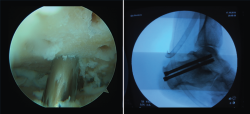

Figura 7. Artrodesis subastragalina artroscópica.

- Artrodesis de tobillo: artrodesis tibiotalar, subtalar…

- Cirugía artroscópica: lesiones osteocondrales, tratamiento artroscópico de la inestabilidad (reparación y técnicas de reconstrucción), endoscopia posterior de tobillo y tendoscopia (Figuras 4, 5, 6 y 7).